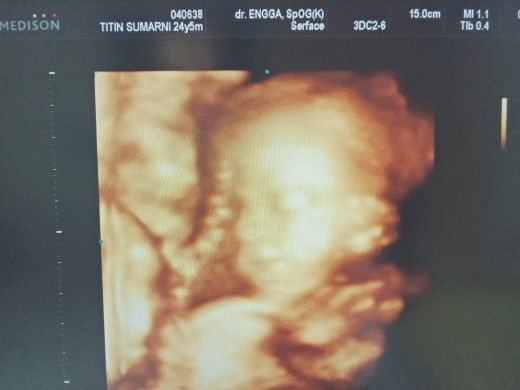

Sore bunda" cantik saya cuma mau berbagi kebahagiaan,ini hasil usg saya Alhamdulillah semua baik,sehat. Ini usg pertama 22w4d. Semoga kita dan baby sehat sampai lahiran ya bun.